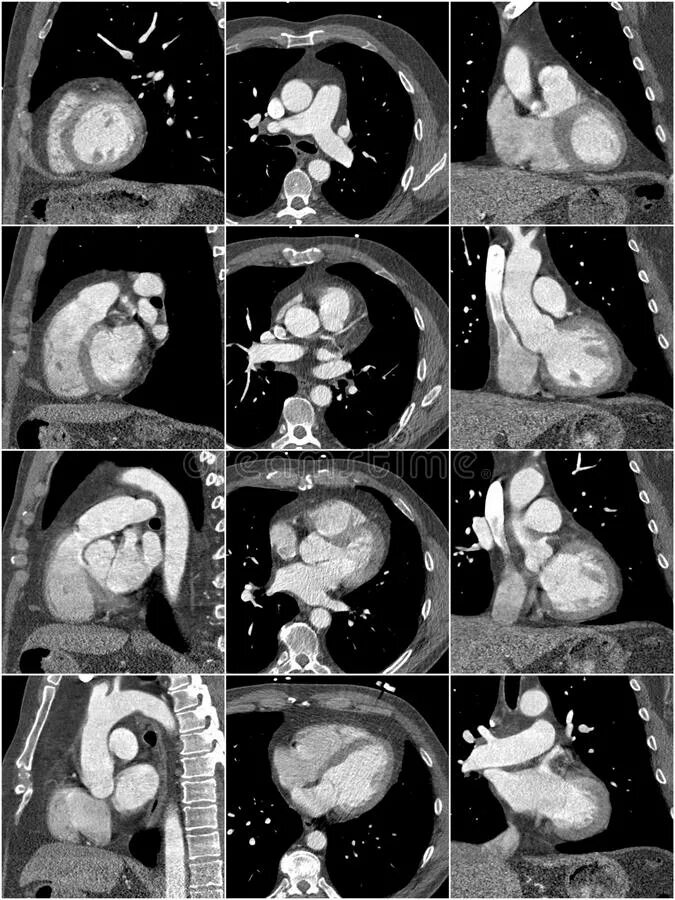

Как делают кт сердца